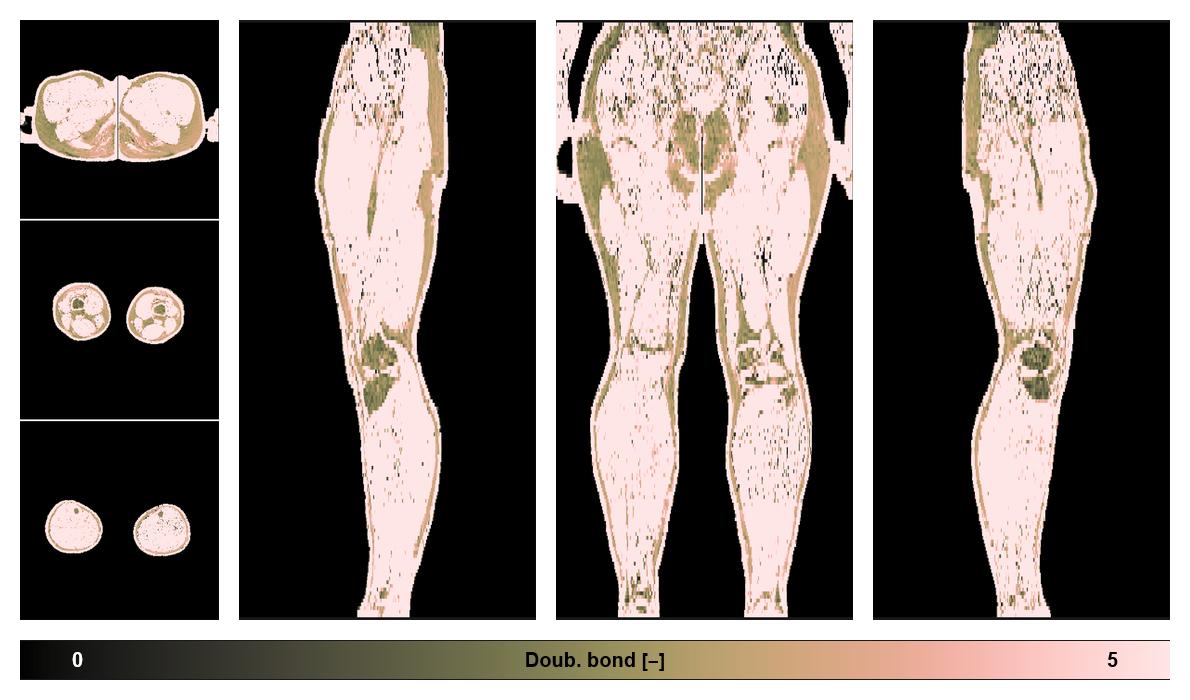

• Number of double bonds in subcutanious fat

Number of double bonds in subcutanious fat.